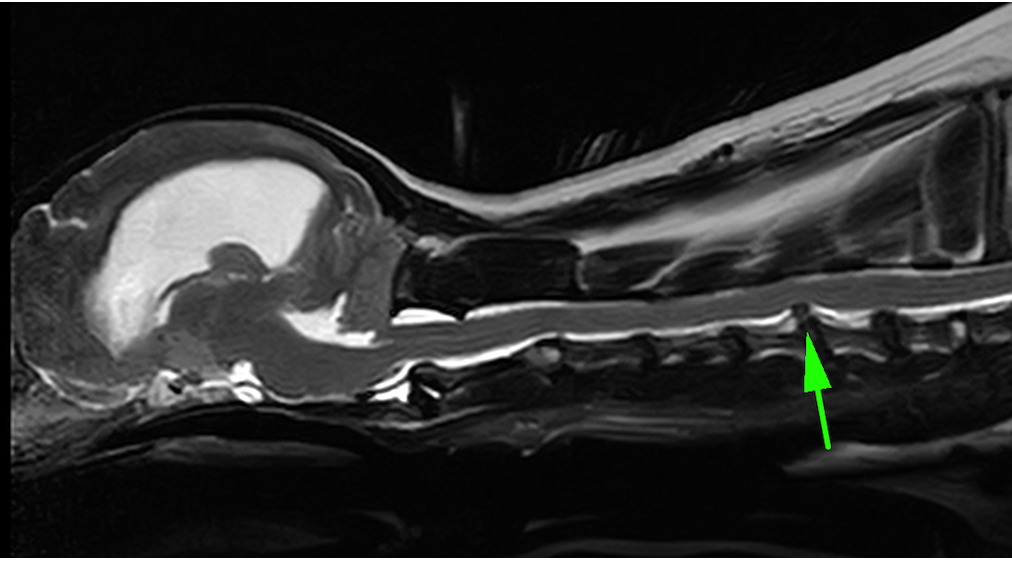

頚部椎間板ヘルニアは頚椎という首の骨をつなぐ椎間板物質が背側に飛び出してしまうことで、そこの神経を圧迫し、疼痛や麻痺を引き起こす疾患です。診断は触診や神経学的検査、レントゲン検査に加え、MRI検査が必須となります。

矢印の部分の椎間板物質が飛び出しているのがわかります。診断名は第5−6頚部椎間板ヘルニアです。

術後のフォローアップMRIです。術前のMRIで突出していた椎間板物質は取り除かれ、スムースになっているのがわかります。